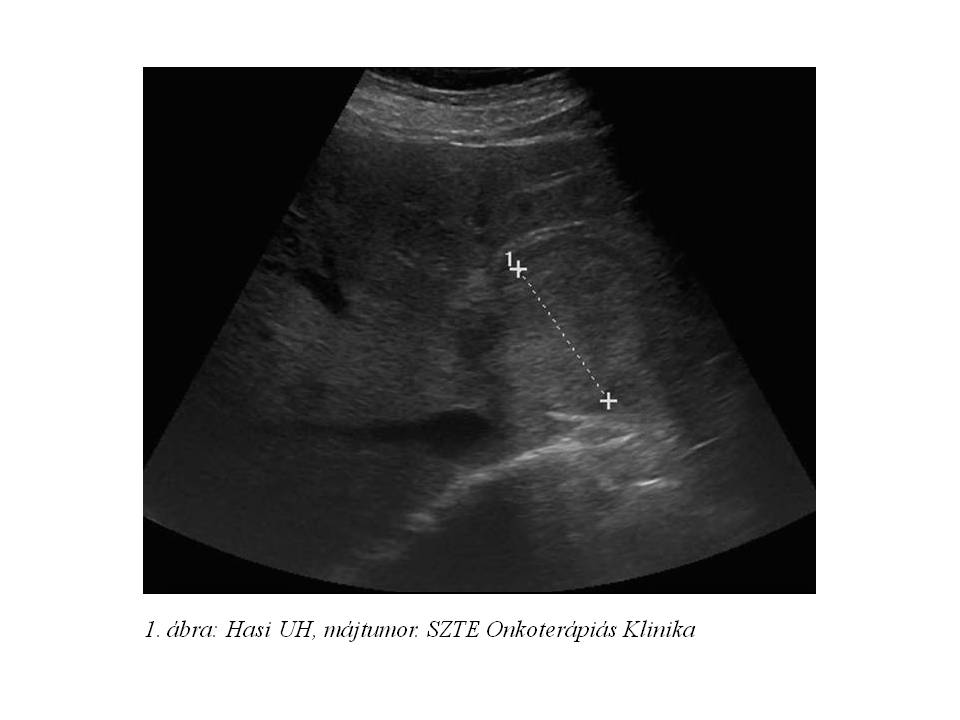

57 éves férfibeteg 2011 júliusában potenciazavar miatti urológiai kivizsgálása során hasi UH (1. ábra) és CT vizsgálat (2. ábra) történt, melyek során a máj bal lebenyében egy 60 mm legnagyobb átmérőjű, ill. számos 10-20 mm-es lézió került leírásra. UH vezérelt májbiopsiát követően szövettan igazolta neuroendokrin malignitását (immunhisztokémiai vizsgálattal CK7: -, CK18: 3+, chromogranin A: 3+, synaptophysin: 3+, CD56: 3+, hepatocyta antigén: -, AFP: -, Ki67: <4%, szerotonin: 1+, VIP: 2+, insulin: -, glucagon: -, somatostatin: -, gastrin: -). Gastrin, chromogranin, vizelet 5HIAA és VMS vizsgálat történt, a chromogranin (>770 ng/ml), vizelet 5HIAA (137,6 mg/24h vizelet) és VMS (18,4 mg/24h vizelet) emelkedett volt. A májban található neuroendokrin tumor primer vagy áttéti mivoltának meghatározása érdekében staging-jét gasztroszkópiával és hasi MR vizsgálattal (3. ábra) is kiegészítették, melyek azonban a máj többgócú folyamatán kívül egyéb eltérést nem detektáltak. Octreoscan vizsgálat ekkor nem történt a somatostatin receptor negativitás miatt.